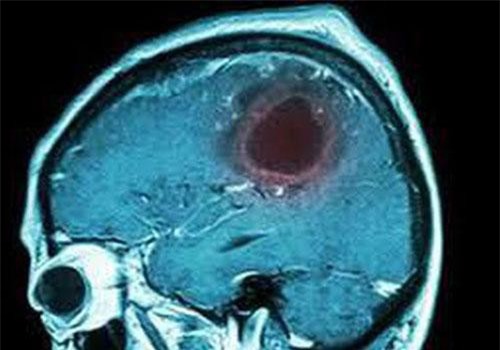

U não là bệnh ảnh hưởng đến cả nam và nữ ở mọi lứa tuổi và chủng tộc. Trong số những bệnh nhân nổi tiếng nhất có thượng nghị sĩ John McCain được chẩn đoán mắc bệnh ung thư não vào năm 2017.